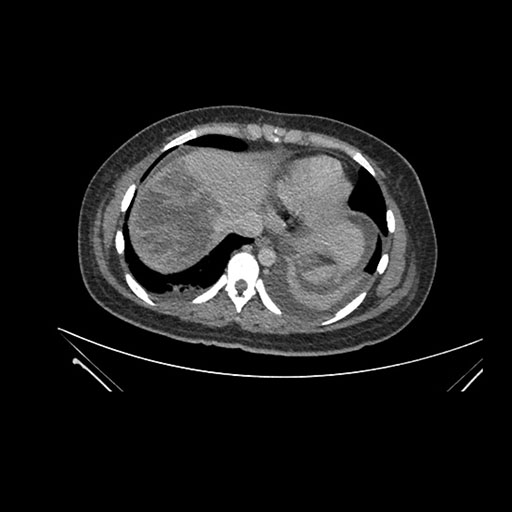

Axial Venous

Imaging analysis

Based on initial findings, which issue(s) would you be most concerned about?